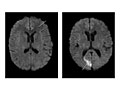

For an MRI of the head, you lie with your head inside a special machine (scanner) that has a strong magnet. The MRI can show tissue damage or disease, such as infection or inflammation, or a tumor, stroke, or seizure. Information from an MRI can be saved and stored on a computer for more study. Photographs or films of certain views can also be made.

- Bleeding or swelling (edema) in or around the brain is present.

- Abnormal areas in the brain may mean that certain diseases, such as Huntington's disease, multiple sclerosis, or Parkinson's disease, are present.